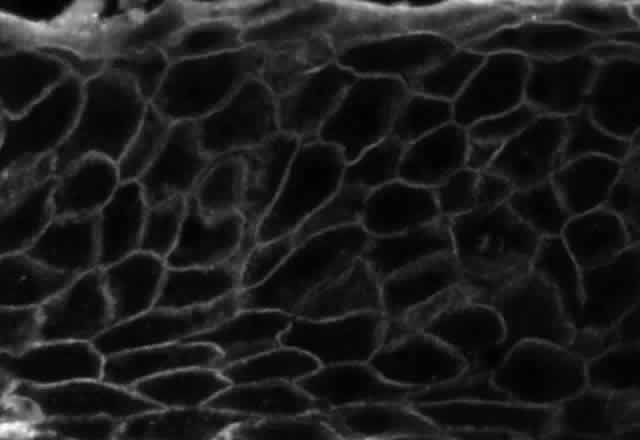

Fig. 3. Immunofluorescence microscopy of conjunctiva from a patient with pemphigus vulgaris. The antibody is a fluorescein-conjugated antibody directed against human IgG. Note the bright staining of the intercellular cement, brightly outlining the borders of all of the epithelial cells.